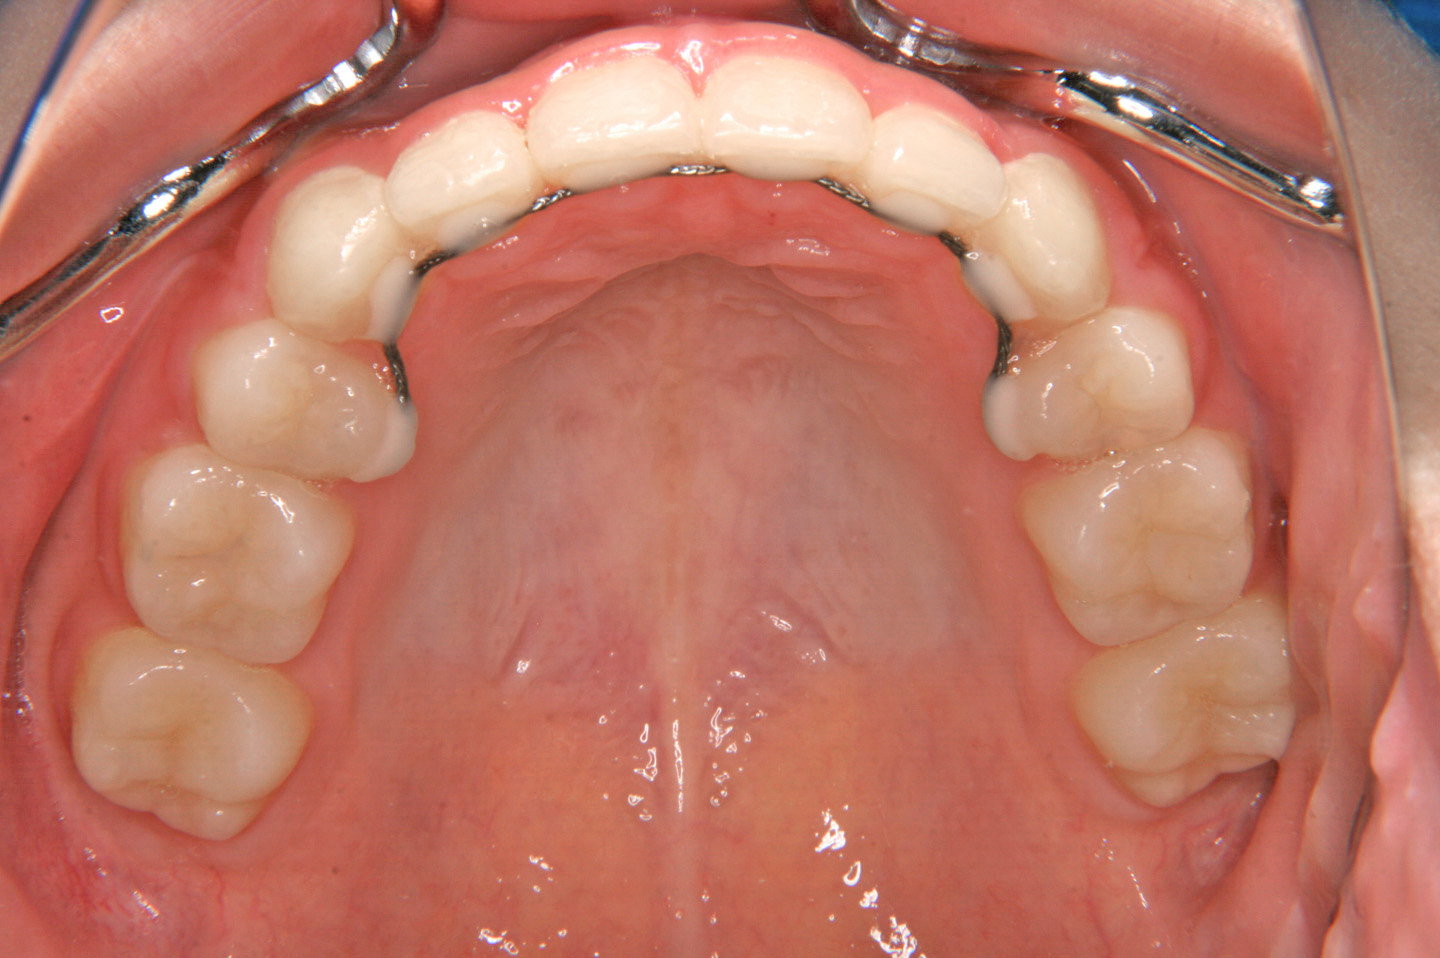

八重歯を気にされて来院された女性です。叢生と上顎前突の改善のため上顎小臼歯2本と、下顎前歯1本を抜歯させていただいて、エッジワイズ装置を用いて歯並びを整えました。現在は、ボンデッドワイヤーとリテーナーを併用した保定に移行しております。

動的治療終了時